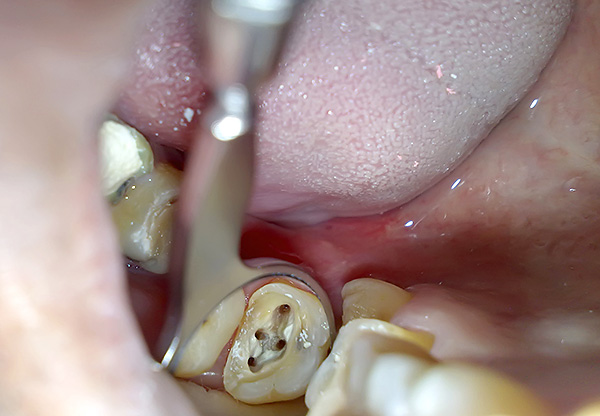

A foto abaixo mostra um exemplo de dente removido com cistos nas raízes:

Em muitos casos, é importante remover o cisto dentário a tempo de evitar o desenvolvimento de complicações graves. Aqui você precisa entender que a formação de um cisto é uma manifestação peculiar da reação protetora do corpo, que tenta isolar a infecção que penetrou no canal radicular do dente nos tecidos circundantes. Primeiro, ocorre um processo inflamatório na raiz do dente, que geralmente passa para o cisto.